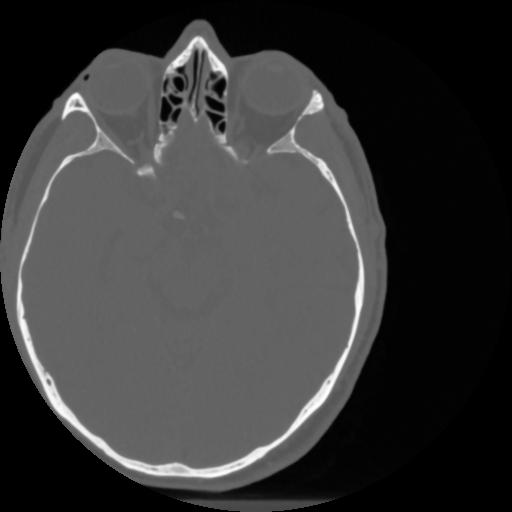

4 CEREBRO,,Vol,0.5,CEREBRO,,